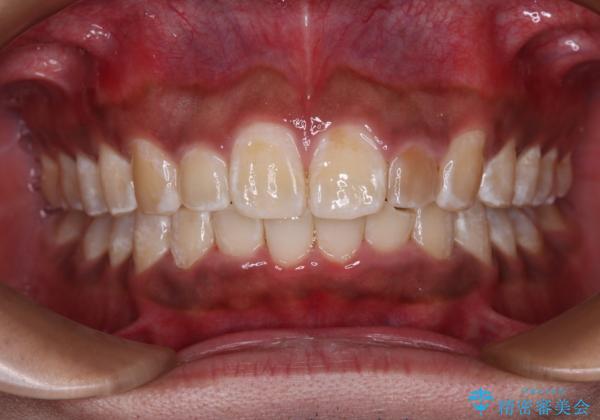

上顎前突とディープバイト ワイヤー矯正での確実に仕上げる

正面や横から見た印象が同じで用であっても、奥歯の咬み合わせが理想的であるかどうかによって、治療の難易度は大きく異なります。

こちらの方も難易度のやや高い状態で、2年以上の期間が予想されましたが、想定通りの2年強で治療を終えることができました。